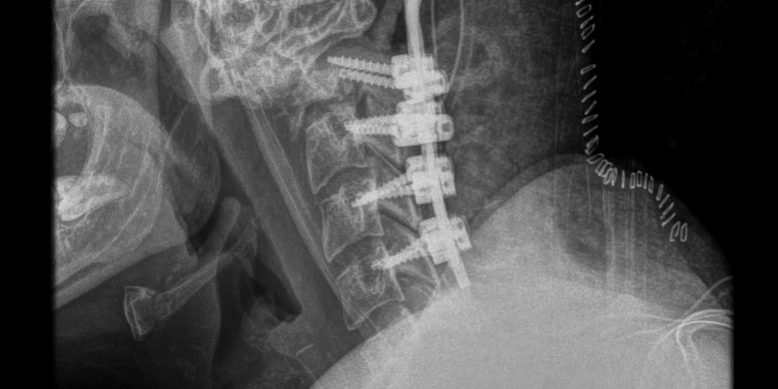

Η μετεγχειρητική πορεία της ασθενούς ήταν ανεπίπλεκτη και ο ασθενής εξήλθε την 3η μετεγχειρητική ημέρα. Η μετεγχειρητική αξονική τομογραφία και ακτινογραφία έδειξε ορθή θέση των μοσχευμάτων και πολύ ικανοποιητική θέση κεφαλής σε σχέση με την ΑΜΣΣ (βλ. εικόνες παρακάτω)

Τα υλικά πρέπει να τοποθετηθούν με απόλυτη ακρίβεια προκειμένω η αυχενική μοίρα του ασθενούς να στηρίξει επαρκώς και σε βάθος χρόνου την κεφαλή. Τοποθετήθηκαν διαυχενικές βίδες (δηλαδή βίδες οι οποίες “πιάνουν” στον αυχένα του σπονδύλου). Η τοποθέτηση των βιδών σε αυτή τη θέση είναι τεχνικά απαιτητική, έχει όμως το πλεονέκτημα ότι προσφέρει τη μέγιστη στήριξη γιατί “πιάνει” σε φλοιώδες οστό (δηλαδή σκληρό οστό) και το μήκος των βιδών μπορεί να είναι πολύ μεγαλύτερο σε σχέση με τις βίδες οι οποίες τοποθετούνται στα πλάγια ογκώματα των αυχενικών σπονδύλων. Συγκεκριμένα, χρησιμοποιήθηκαν βίδες 18-20 χιλ. (έναντι 12 έως 14 χιλ). Αυτό επετεύχθη με τη βοήθεια διεγχειρητικής νευροπλοήγησης (O-arm). Με τον τρόπο αυτό αποφύγαμε μεγαλύτερο μήκος σπονδυλοδεσίας, το οποίο θα ακινητοποιούσε ακόμη περισσότερο τον αυχένα του ασθενούς.